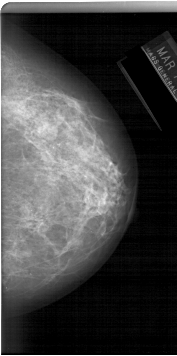

A_1233_1.RIGHT_MLO

RIGHT_CC LINES 6391 PIXELS_PER_LINE 3181 BITS_PER_PIXEL 12 RESOLUTION 43.5 NON_OVERLAY